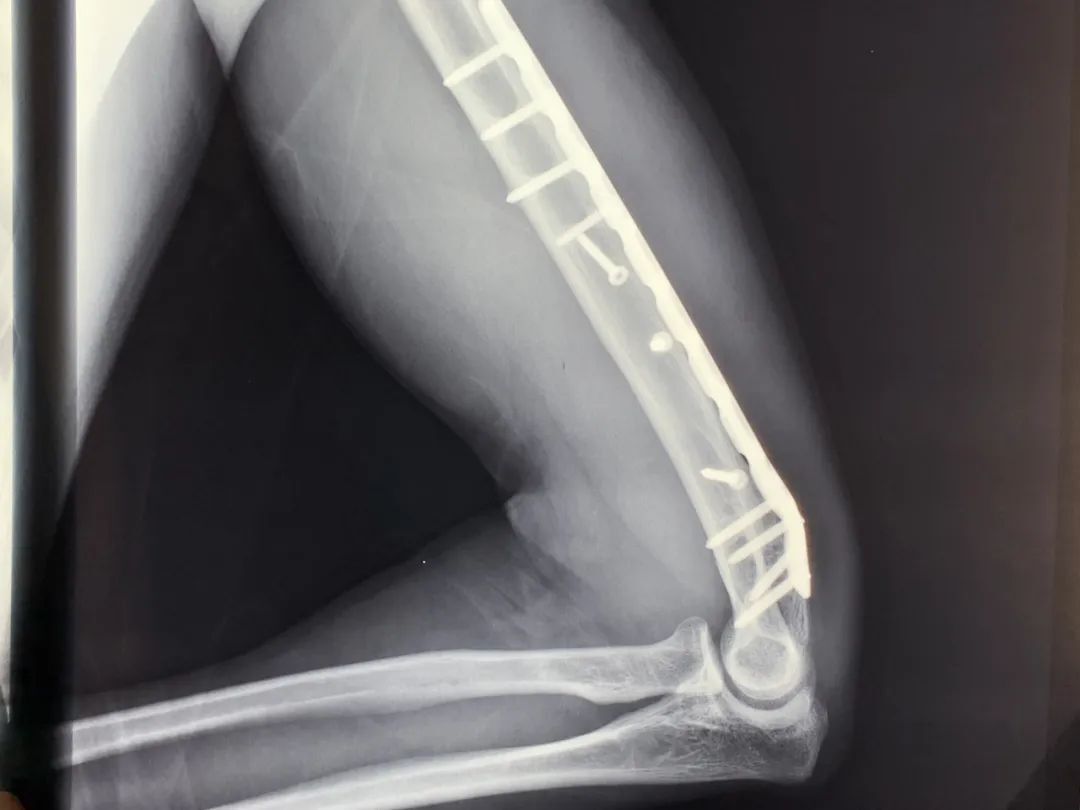

在奋力压制恶徒的过程中毕光熙突然感觉右臂一阵剧痛待到将恶徒制服后起身毕光熙发现自己的右臂已经明显变形事后检查显示“肱骨被拧断成了麻花状”11根钢钉、20厘米钢板永久保留在体内同事将他紧急送往医院拍完X光片医生给出了伤情结论:“右臂肱骨粉碎性骨折”原本预计3个小时的手术整整延长一倍时长20厘米长的钢板11根钢钉被植入固定在骨折处

由于固定伤处的钢板距离桡神经过近产生粘连拆除钢板或会导致神经受损进而影响右臂功能医生建议将其永久保留体内“下一次还是会往前冲这是我的责任!”如今毕光熙右臂弯曲时右手手指只能刚刚触碰到肩部因为担心压到钢板睡觉时无法向右侧卧23厘米的疤痕20厘米的钢板11根钢钉一张蓝色残疾证……将伴随他的一生